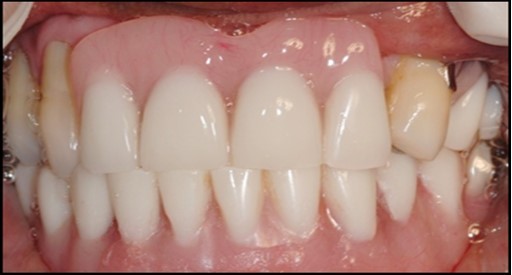

A transferable mark with an indelible pencil is placed on top of each ball abutment and old denture is seated to ideally determine the location for attachment housings. It is followed by preparation of recesses in the intaglio surface of the denture to accommodate the housings (Figure 7B). Lingual vent holes are made for escape of excess acrylic. Placement of nylon processing insert into each of the housings is done with insert seating tool. Figure 8 Seating of the attachment housing onto each ball type abutment is done (Figure 9). Undercuts are blocked out under the housing and soft tissue to prevent acrylic resin from locking the denture onto the abutment. Application of self curing acrylic is done into recessed area and around titanium housings for bonding of the housings to denture. Insertion of denture was done and guiding the patient into proper occlusion with the opposing arch. After the curing of acrylic, denture is removed. Excess acrylic is removed around the housings and lingual vent hole later it is polished (Figure 10). Replace nylon retention insert instead of processing insert into the housings. The insert must seat securely in place and be in level with the housings rim. Overdenture is seated over the ball abutments (Figure 11). Proper instructions have been given to the patient on insertion and removal of prosthesis (Figure 12). The patient was recalled at 1 week, 3 weeks, 3 months, 6 months follow up appointments.

General criteria for survival and success of implants have been used to evaluate the efficacy of immediately loading mandibular implants. For example, survival criteria include how the implant performs, particularly regarding the absence of pain, infection, and paresthesia. Implant immobility and the absence of periimplant radiolucency under radiography are 2 more criteria of implant survivability.6, 7 Success criteria include the additional element of absence of vertical bone loss; specifically, less than 1 mm during the first year and less than 0.2 mm annually thereafter. Granted that success rates for immediatel oading of implants in the edentulous mandible are not as high as rates for the traditional 2-stage approach, conditions nevertheless often warrant the 1-stage surgical option described here.7, 8, 9 (Figure 12).

Using 2 implants and retentive anchors for the retention of a mandibular complete denture is, in terms of immediate costs, one of the most affordable implant procedures. 8, 9, 14 With ideal placement of the implant, the stability of the prosthesis is excellent and the lingual dimensions of the denture can in some cases be reduced to the level of mylohyoid line, providing more space for the tongue and greater comfort than with conventional complete dentures.8, 9, 10, 15 However, if the labial musculature is tense or the amount of attached gingiva is limited, the implants should not be placed too deep or too labially, which might prevent gingival growth over the abutments. In those cases, ball anchor abutments with elevated shoulders can be used to improve implant anatomy.8, 9, 10 (Figure 12).

In conclusion, within the limits of this interim report, immediate loading of two-implants supporting a locator retained mandibular overdenture seems to be a suitable treatment option. The marginal bone level changes around immediately loaded implants are comparable to those seen around implants loaded with a torque do not effect peri-implant bone loss. Implant survival of immediately loaded implants may be lower than those loaded with a delayed protocol, but this needs to be confirmed in future investigations with a larger sample size. Elayed protocol, at 6 months postsurgery. Implant length and peak insertion.